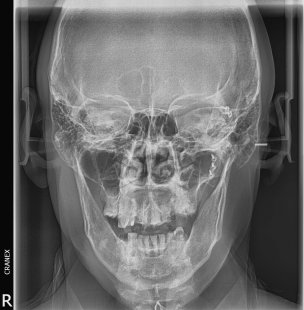

- RX. Frontal (Postero-anterior)